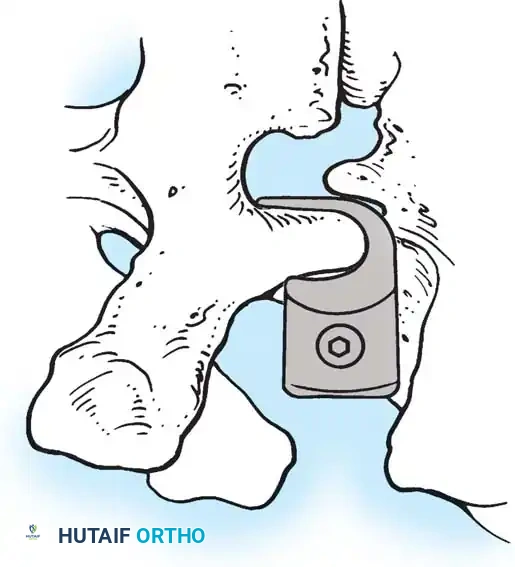

The Hall Technique

The Hall technique offers an alternative method for facet obliteration and grafting, particularly useful in rigid deformities.

Fig. 38-28: The Hall technique of facet fusion, involving sharp excision of the inferior facet and trough creation.

- Sharply amputate the inferior articular facet with a gouge and remove the bone fragment entirely. This exposes the cartilage of the superior facet.

- Remove the exposed cartilage completely with a sharp curet.

- Create a bleeding trough by removing the outer cortex of the superior facet.

- Impact cancellous bone grafts directly into this vascularized trough.

- Complete the procedure with global decortication of the posterior elements.